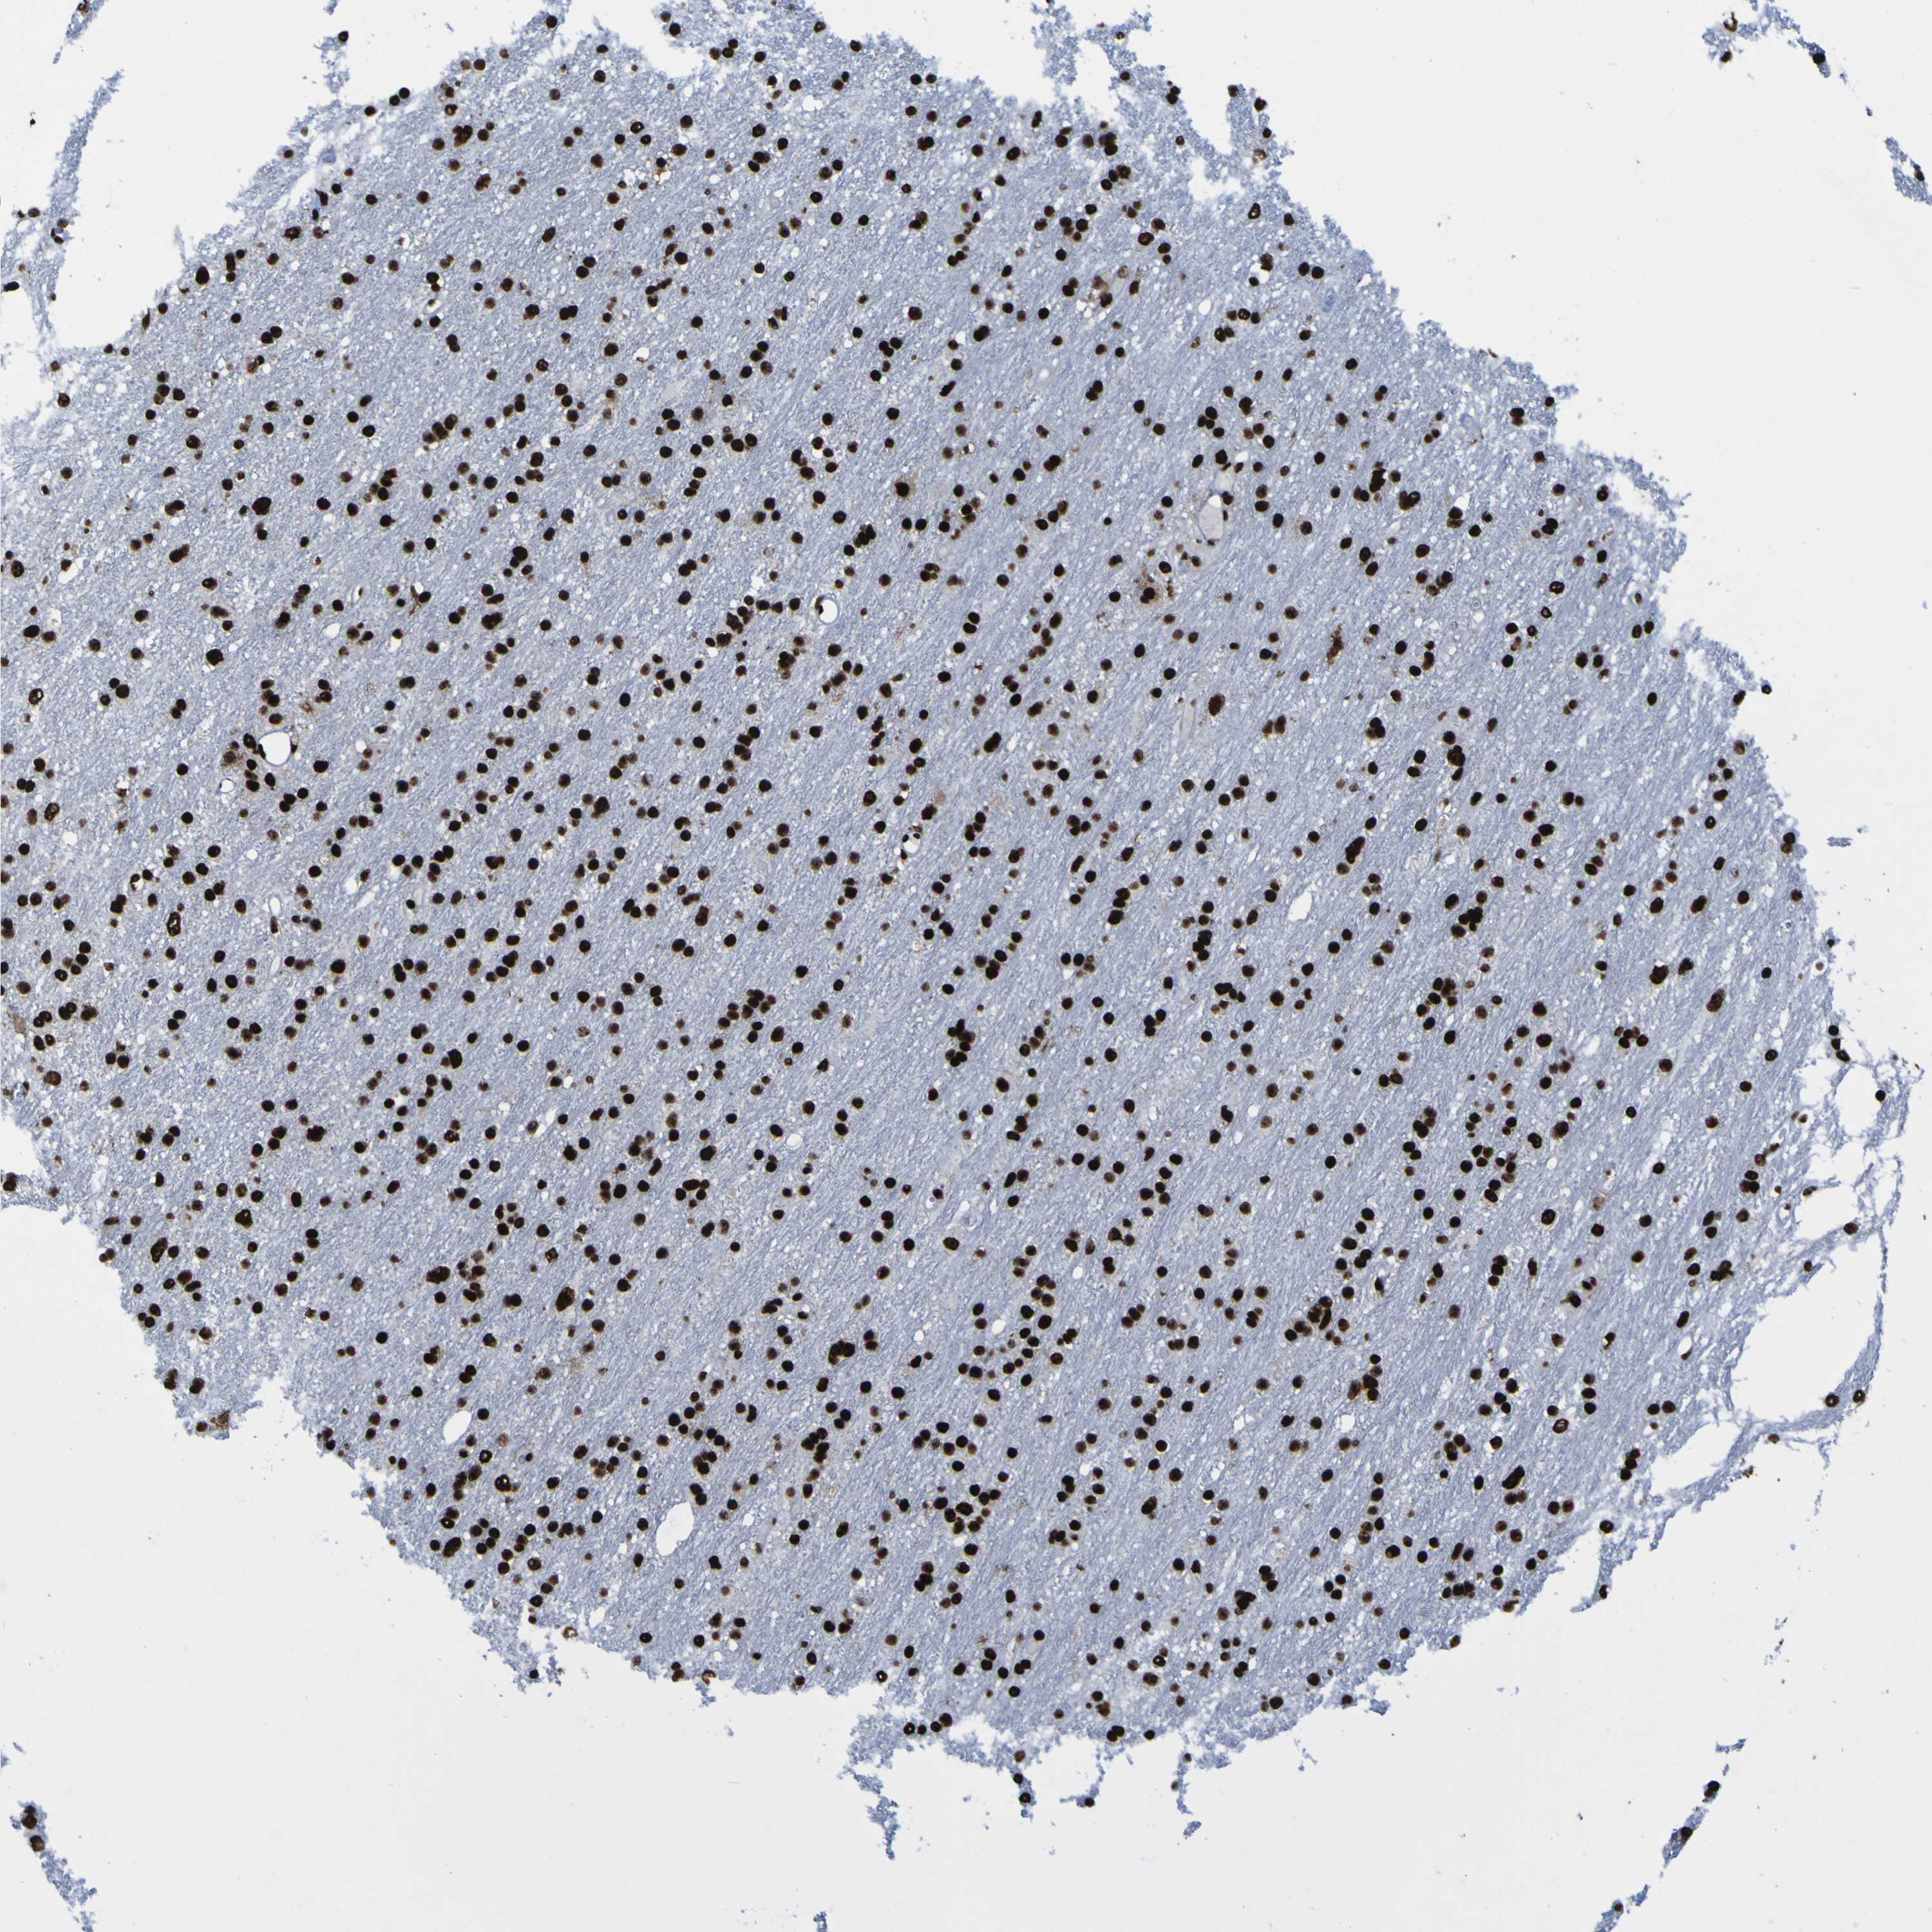

GLIOMA - Protein expressioni

A mouse-over function shows sample information and annotation data. Click on an image to view it in a full screen mode. Samples can be filtered based on level of antibody staining by selecting one or several of the following categories: high, medium, low and not detected. The assay and annotation is described here.

Note that samples used for immunohistochemistry by the Human Protein Atlas do not correspond to samples in the TCGA dataset.

Antibody stainingi

Antibody staining in the annotated cell types in the current human tissue is reported as not detected, low, medium, or high, based on conventional immunohistochemistry profiling in selected tissues. This score is based on the combination of the staining intensity and fraction of stained cells.

Each image is clickable and will lead to virtual microscopy that enables deeper exploration of all samples and also displays staining intensity scores, fraction scores and subcellular localization as well as patient and tissue information for each sample.

Antibody HPA011384

Antibody CAB012983

Staining

High

Medium

Low

Not detected

Intensity

Strong

Moderate

Weak

Negative

Quantity

>75%

75%-25%

<25%

None

Location

Nuclear

Cytoplasmic/membranous

Cytoplasmic/membranous,nuclear

Glioma, malignant, High grade

Glioma, malignant, Low grade